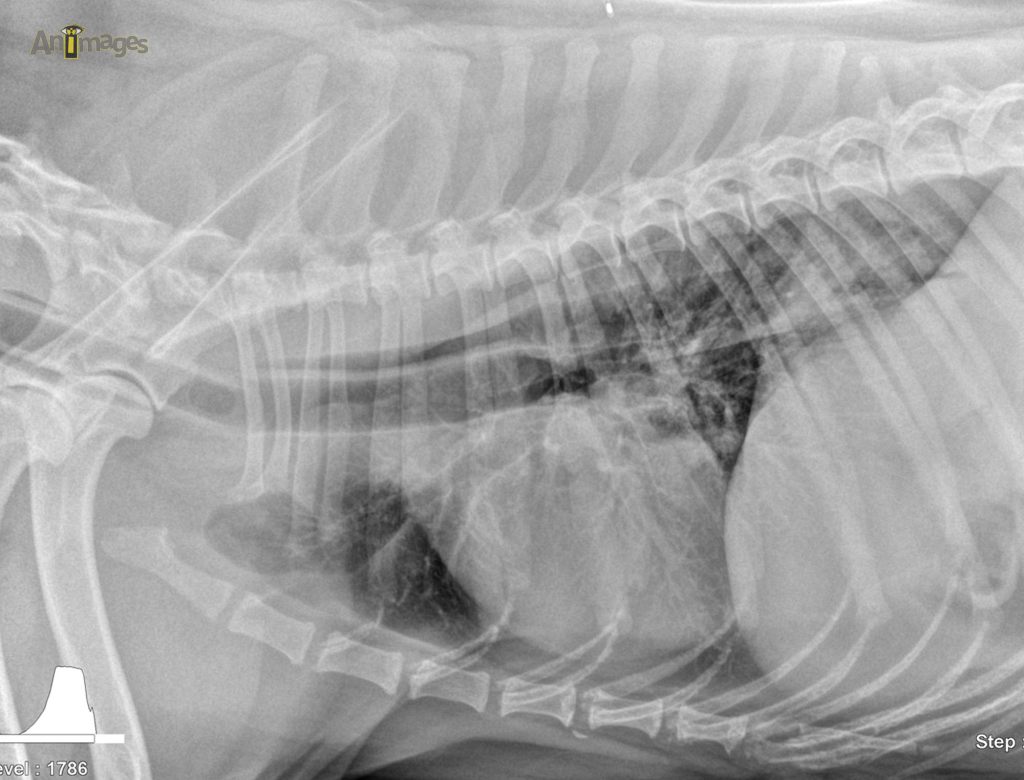

Latérale gauche